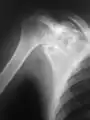

A variety of imaging studies can be used to diagnose chondroblastoma, with radiographs being the most common.[10][8] Laboratory studies are not considered useful.[14] Classical chondroblastoma (appearing on long bones) appears as a well-defined eccentric oval or round lytic lesion that usually involves the adjacent bone cortex without periosteal reaction.[10][13] A sclerotic margin can be seen in some cases.[10][13] For long bone chondroblastomas the tumor is typically contained to the epiphysis or apophysis but may extend through the epiphyseal plate.[10][13] Chondroblastomas are usually located in the medullary portion of bones and can, in some cases, include the metaphysis.[10][13] However, true metaphyseal chondroblastomas are rare and are typically the result of an extension from a neighboring epiphyseal legion.[10][13] Most lesions are less than 4 cm.[10] A mottled appearance on the radiograph is not atypical and indicates areas of calcification which is commonly associated with skeletally immature patients.[10] Additionally, one-third of all cases involve aneurysmal bone cysts which are thought to be the result of stress, trauma or hemorrhage.[10] In cases involving older patients or flat bones, typical radiographic presentation is not as common and may mimic aggressive processes.[10][13]